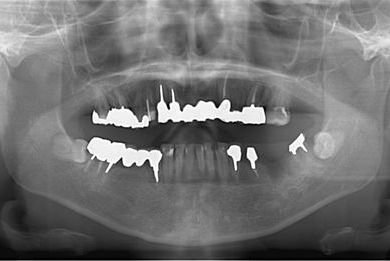

インプラントの症例写真 IMPLANT

骨再生インプラント治療

| 主訴 | 右下のブリッジが外れているかもしれないという診断を受けましたが、開けてみないとわからない、場合によっては部分入れ歯と言われ、セカンドオピニオンを希望。腫れがあるのも気になります。 | ||||||||||||||||||||||||||||||||

| 治療方針 | 右下奥、骨再生法によりインプラント治療を可能にする。 | ||||||||||||||||||||||||||||||||

| 治療内容 | インプラント3本(GBR、テンポラリーインプラント+仮歯)、ハイブリッドセラミックブリッジ3本、ハイブリッドセラミッククラウン2本 | ||||||||||||||||||||||||||||||||